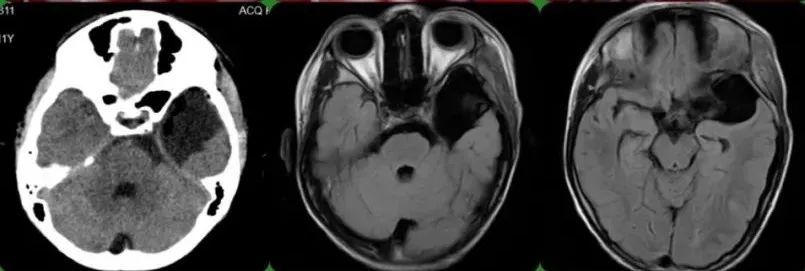

术后检查

术后,家长诉男孩术后无肢体不自主抖动, 复查头颅MRI检查示:左侧中颅窝蛛网膜囊肿术后状态,囊肿范围较术前缩小。